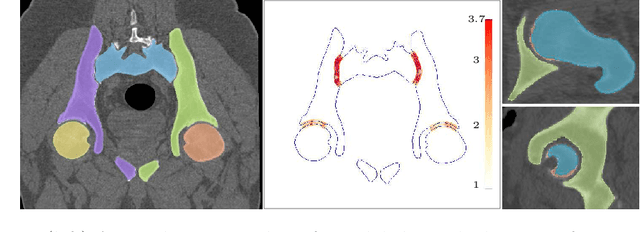

Abstract:Accurate geometry representation is essential in developing finite element models. Although generally good, deep-learning segmentation approaches with only few data have difficulties in accurately segmenting fine features, e.g., gaps and thin structures. Subsequently, segmented geometries need labor-intensive manual modifications to reach a quality where they can be used for simulation purposes. We propose a strategy that uses transfer learning to reuse datasets with poor segmentation combined with an interactive learning step where fine-tuning of the data results in anatomically accurate segmentations suitable for simulations. We use a modified MultiPlanar UNet that is pre-trained using inferior hip joint segmentation combined with a dedicated loss function to learn the gap regions and post-processing to correct tiny inaccuracies on symmetric classes due to rotational invariance. We demonstrate this robust yet conceptually simple approach applied with clinically validated results on publicly available computed tomography scans of hip joints. Code and resulting 3D models are available at: https://github.com/MICCAI2022-155/AuToSeg}